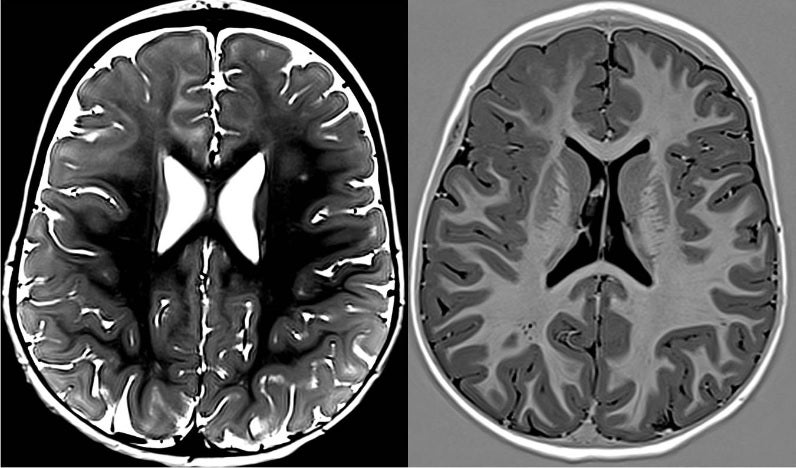

El especialista destaca que casi todos estos pacientes venían con resonancias magnéticas cerebrales informadas como normales, y electroencefalogramas que mostraban alteraciones generalizadas, con lo cual era imposible sospechar que existía una zona del cerebro enfermo y que el resto del cerebro estaba sano.

«Parecía que todo el cerebro estaba enfermo, pero cuando nosotros estudiábamos a estos niños con nuestra perspectiva clínica, nos encontrábamos que aquello que se había considerado generalizado no lo era. En realidad, su epilepsia se originaba en un solo foco, que podía ser más o menos amplio, y que propagando al cerebro sano impedía que éste se desarrollase con normalidad o incluso causaba la perdida de funciones ya adquiridas», reconoce el Dr. Gil-Nagel Rein.

Este experto en epilepsia y referente internacional en la asistencia, divulgación e investigación en epilepsia, subraya que una vez que tenían esta sospecha, y dirigían su atención a la zona localizada en el EEG y por los síntomas observados en sus crisis, podían apreciar alteraciones sutiles en las imágenes de resonancia magnética y el PET cerebral. «Estas alteraciones podían englobarse dentro de lo que ya conocíamos como malformaciones del desarrollo cortical, pero eran mucho menos evidentes».